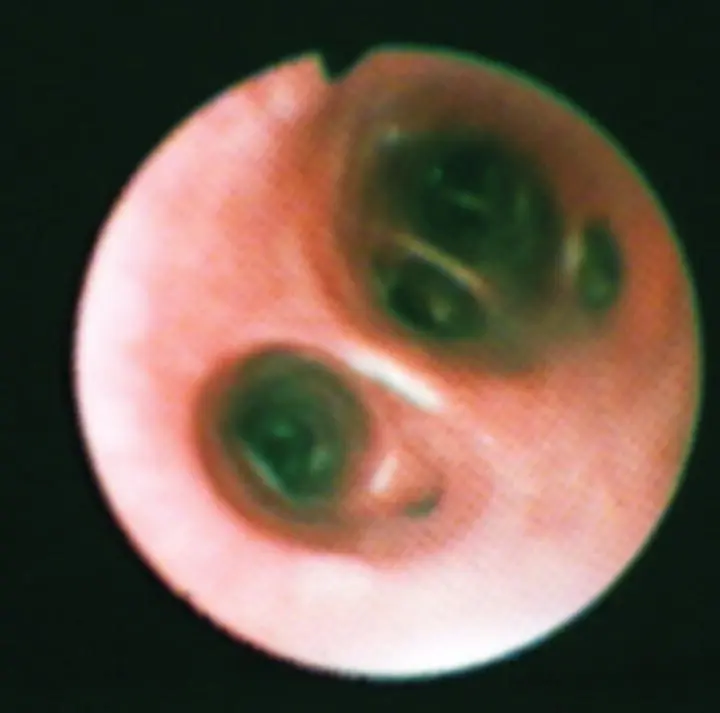

After examining all visible airways, the scope is withdrawn from the airways, the outside is wiped with saline‐soaked gauze pads, and the biopsy channel is flushed with sterile saline. On the second entry to the airway, the scope should be kept in the center of the airways to limit upper airway and mucosal contamination when approaching the site for lavage. Success in achieving a diagnostic BAL will depend on the ability to wedge the bronchoscope gently into a small airway and isolate a segment of alveolar volume ( Figure 2.22). The goal is to flood this small wedge of lung with sterile non‐bacteriostatic saline, float the resident inflammatory cells, and gently aspirate back the fluid. Fluid should be fully ejected from the scope into the alveolar space by flushing gently with a small volume of air (3–5 ml) before beginning the aspiration. The volume of fluid used depends on the size of the scope in relation to the size of the animal, experience of the operator, underlying disease process, and degree of respiratory compromise ( Table 2.4), although ~1 ml/kg has been also recommended. If the fluid has been in contact with the alveolar space, it will be foamy because of the presence of surfactant. Flocculent material is usually mucus from bronchial contamination. If a sufficient sample is not recovered from the lavage (generally 50–70% of the fluid will be recovered), a second lavage should be performed at the same site. In human medicine, multiple lavages are commonly obtained and the first is not analyzed, because it represents more of the bronchial component rather than alveolar. It is unclear how often this is done in veterinary medicine. It is recommended to lavage at least two distinct lung sites because of inherent differences in the inflammatory cell populations among the lung lobes and with different disease processes.

Figure 2.22 Bronchoalveolar lavage (BAL) is performed by gently wedging the bronchoscope into the smallest airway possible. The volume of the region lavaged (represented by red and yellow triangles) will depend on the size of the scope and the size of the animal.